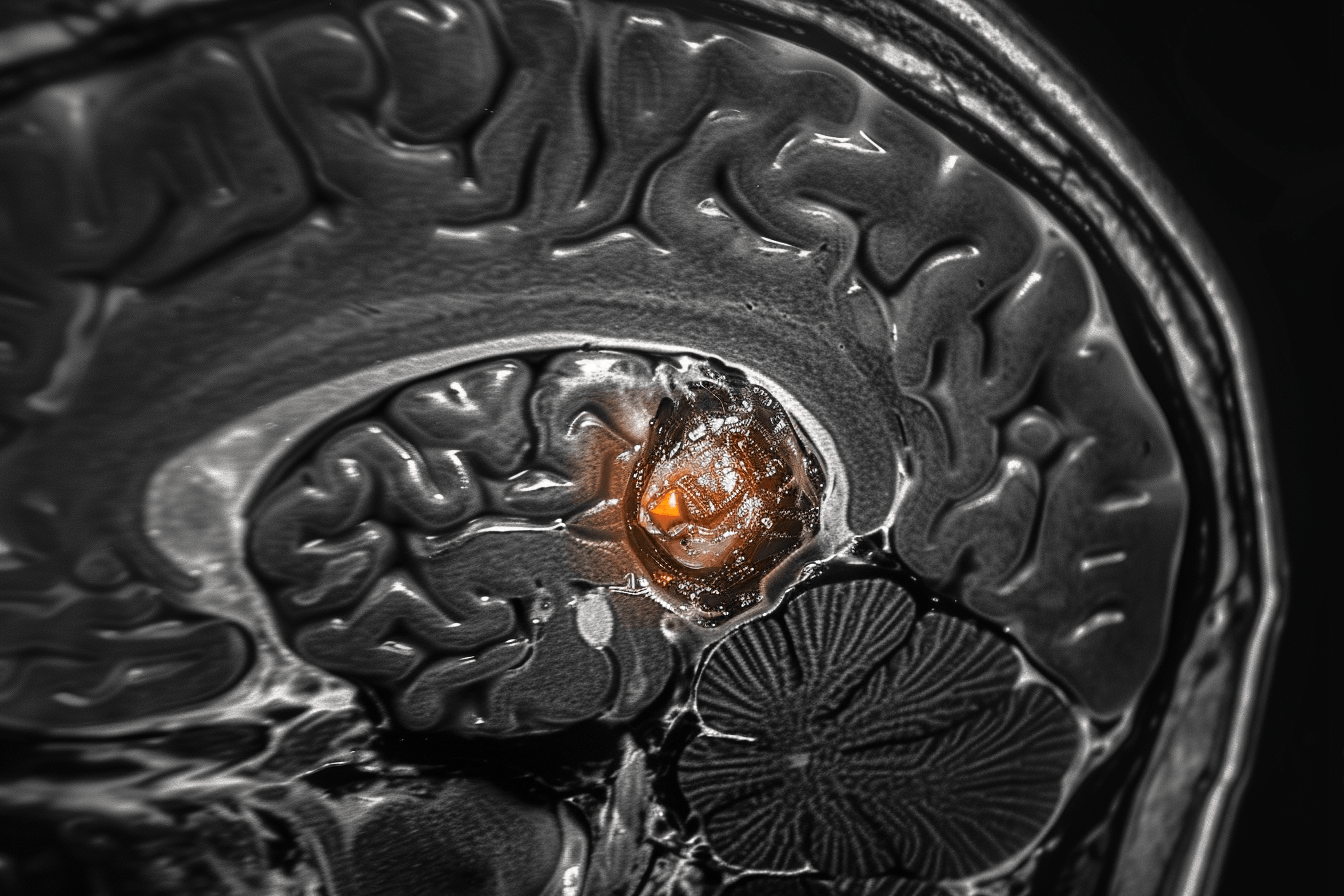

Another important limitation is how monitoring works. MRI scans are designed to detect structural changes in the brain, not early biological activity. According to clinical evidence, tumor cells can begin growing again long before they become visible on imaging [9]. This means that by the time recurrence is confirmed, the disease may already be progressing for months.

Months before glioma recurrence is visible on a scan, the process has already started inside the brain. After treatment, small clusters of tumor cells remain hidden within normal brain tissue. These cells slowly begin to divide and expand, but at a scale too small to be detected on MRI. During this time, the patient may feel stable and reports may appear normal, yet biologically the tumor is already regrowing and preparing for visible recurrence [2].

During this hidden phase, the brain is already undergoing subtle but important changes. Tumor cells increase their activity and begin forming new blood supply to support growth. There are also early metabolic changes in the surrounding brain tissue, along with mild disruption of normal brain function. However, these changes are not yet visible on routine imaging, because MRI scans detect structural abnormalities rather than early biological activity.

After treatment ends, most patients enter a monitoring phase that relies primarily on MRI scans. MRI is an excellent tool for visualizing structural changes in the brain, such as tumor size, swelling, or shifts in surrounding tissue. However, the fundamental limitation is that MRI does not detect early biological activity.

In the months following treatment, tumor cells may already be active at a microscopic level. These cells can begin dividing, altering local metabolism, and interacting with surrounding brain tissue. Yet none of these early processes are visible on standard MRI. By the time MRI shows a clear abnormality, the disease has often progressed beyond its earliest stage [9].

This creates a critical delay. From a clinical perspective, the tumor appears stable. But from a biological perspective, recurrence may already be underway.